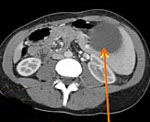

D73.4 Киста селезенки